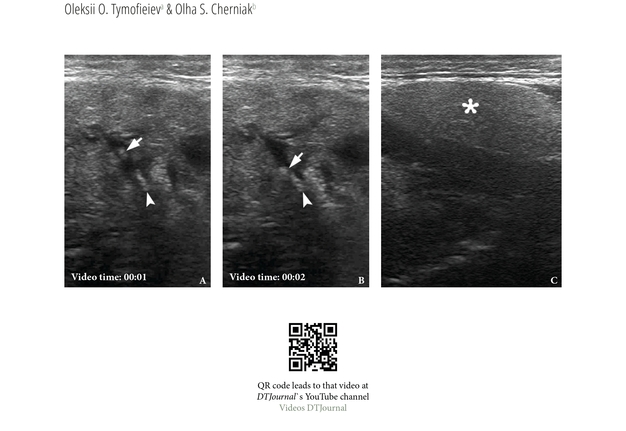

The experience of the NEJM proves that articles of the “Images” type are successfully cited in journals indexed by Scopus [7, 27]. In particular, an article entitled “Lemierre's Syndrome” (Walkty and Embil, 2019) has received 23 citations (Fig 1) in other journals indexed by Scopus since its publication (i.e., 6 years ago). Articles of type “Images” of the JDTOMP also demonstrate the presence of citations in journals indexed by Scopus (Figs 2 and 3) [16, 28]. Although of course the frequency of citations is also affected by the availability of journal articles for search by authors in PubMed/PubMed Central according to the journal sample. Although, of course, the frequency of citations is also affected by the availability of journal articles for search by authors in PubMed/PubMed Central, as is the case with the NEJM [29].

16. Tymofieiev OO, Cherniak OS. Ultrasound in the detection of floating sialoliths. J Diagn Treat Oral Maxillofac Pathol 2019;3(8):196-197. https://doi.org/10.23999/j.dtomp.2019.8.2